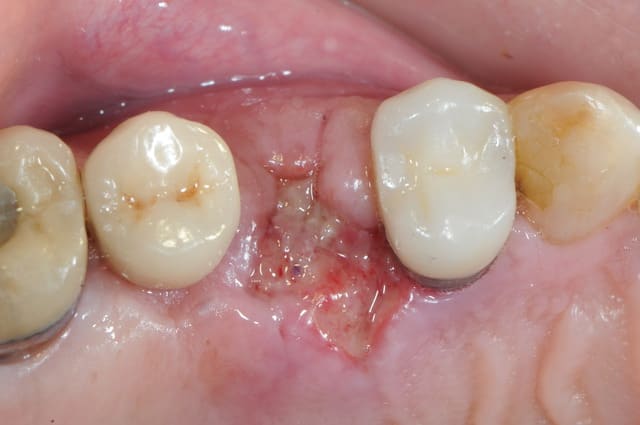

ton intervention, albert, me rappel un cas clinique que j'aimerai partager avec vous:

1-2-3 prémolaire foutu juste à proximité d'un implant, faut donc faire gaffe aux tissus environnant.

en plus je suis sure que la corticale vestibulaire est K.O elle aussi.

4-5: eh ben oui, elle est détruite! une simple curette insérée dans l'alvéole permet de visualiser l'importance de la perte osseuse vestibulaire.

que faire ??

je poursuis donc mon cas clinique si vous voulez bien.

1- curette en appuie sur la face vestibulaire montrant la destruction osseuse.

2- lambeau pleine épaisseur en palatin pour aller chercher un bout de conjonctif qui soit pédiculé.

3 je décole à partit des rebords de la déhiscence osseuse et reste en contacte permanent avec la corticale osseuse tout en décollant la gencive (elle est soulevé donc)

4- comblement avec de la poudre de perlin-pin-pin

( désolé je suis pas au cabinet et je sais plus ce que j'ai mis dedans)

5-6- sutures du conjonctif pour obtenir l'étanchéité (enfin , on essaye)

7- résultat à j+7

17/09/2011 à 20h19

merci céramique!

c'est peut être un hasard, mais le patient est justement passé aujourd'hui. j'en ai bien sure profité pour faire une photo...

on est ici à j+5 mois, pas de perte osseuse vestibulaire.

la pose d'implant ( flapless très certainement) est prévue pour dans 15 jours.